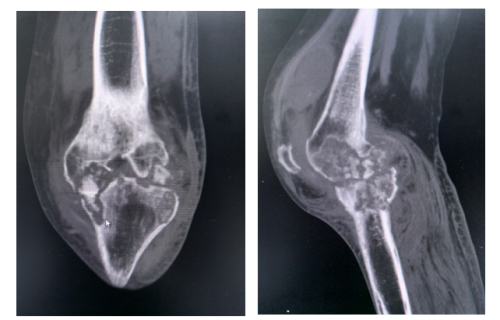

57岁的张云(化名)左膝关节反复肿痛已有两年。她每次上下楼梯、下蹲时疼痛就会加剧,休息后有所缓解,她一直以为是普通关节炎,痛得厉害时就贴贴膏药,做做热敷。三个月前,她的左膝关节外侧皮肤开始破溃,不断流出黄白色脓液,溃疡面越来越大,这才意识到情况不妙。来到长沙市中心医院经系统检查后,结果令人震惊:张云被确诊为“左膝关节结核伴关节腔积液”,同时还发现她患有“双肺继发性肺结核”“支气管扩张”和“左侧肌间静脉血栓”等。而左膝关节的肿胀与破溃,正是结核菌侵蚀骨骼、关节,并穿透皮肤所致。

另一位患者的病情更为复杂。55岁的高海(化名)两年前出现左膝关节肿痛,辗转求医但始终未明确病因。一个月前因严重胸闷、气促入住长沙市中心医院结核病诊疗中心,被诊断为“结核性心包炎”“左膝关节结核伴关节腔积液”“冠心病”“心力衰竭”等多种疾病。虽然抗结核治疗让他的心脏情况有所好转,但左膝关节的疼痛却丝毫未减。这说明膝关节内的结核病灶非常顽固,仅靠药物已难以根除,必须通过手术干预。患者随即转入创伤、关节、骨病科。11月6日,骨科团队迎难而上,在全麻下为他施行“左膝关节结核病灶清除+膝关节骨水泥假体置换+左小腿病灶清除术+VAC负压引流术”。手术不仅彻底清除了结核病灶,还一次性置入骨水泥假体,同步解决了感染控制与关节功能两大难题。